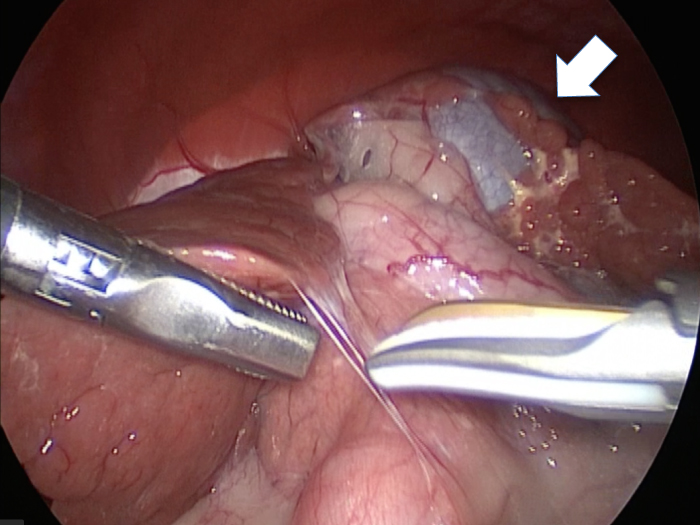

癒着(矢印)がひどく胆嚢を確認することができませんでした。

このように癒着しているときはギリギリで剥がすとひどく出血をおこすことがあるので無理にはがそうとしないで、脂肪の血管に注意しながら脂肪ごと剥がしていきます。

胆嚢の通路がちゃんと開通しているのか調べるために造影検査をしています。

この処置をすることで洗浄の効果と詰まりを確認することができます。